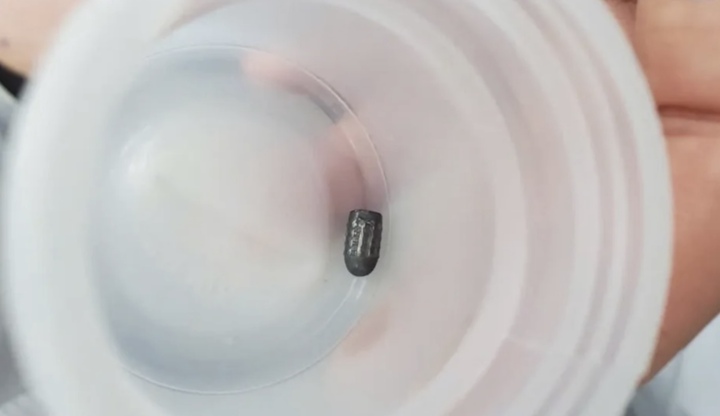

Khi đang làm vườn, người phụ nữ bất ngờ bị dị vật găm vào đầu phải đi cấp cứu, bác sĩ phát hiện dị vật là một đầu đạn kim loại nằm dưới da vùng chẩm.